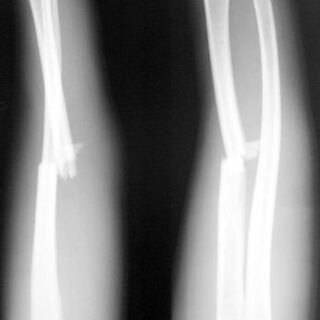

В большинстве случаев переломы конечностей у детей происходят по типу перелома «зеленой ветви».

Внешне такой перелом выглядит в виде надломанной и согнутой кости.

Отличительной чертой такого вида травм является односторонний перелом с небольшим смещением или без него. Это связано с тем, что плотная, но эластичная надкостница как мягкая кора крепко держит оба обломка и не дает им окончательно разделиться.

Поэтому при минимальном подозрении на перелом руки у ребенка необходима срочная консультация специалиста – абсолютная достоверность наличия перелома определяется только при рентгеновском исследовании.